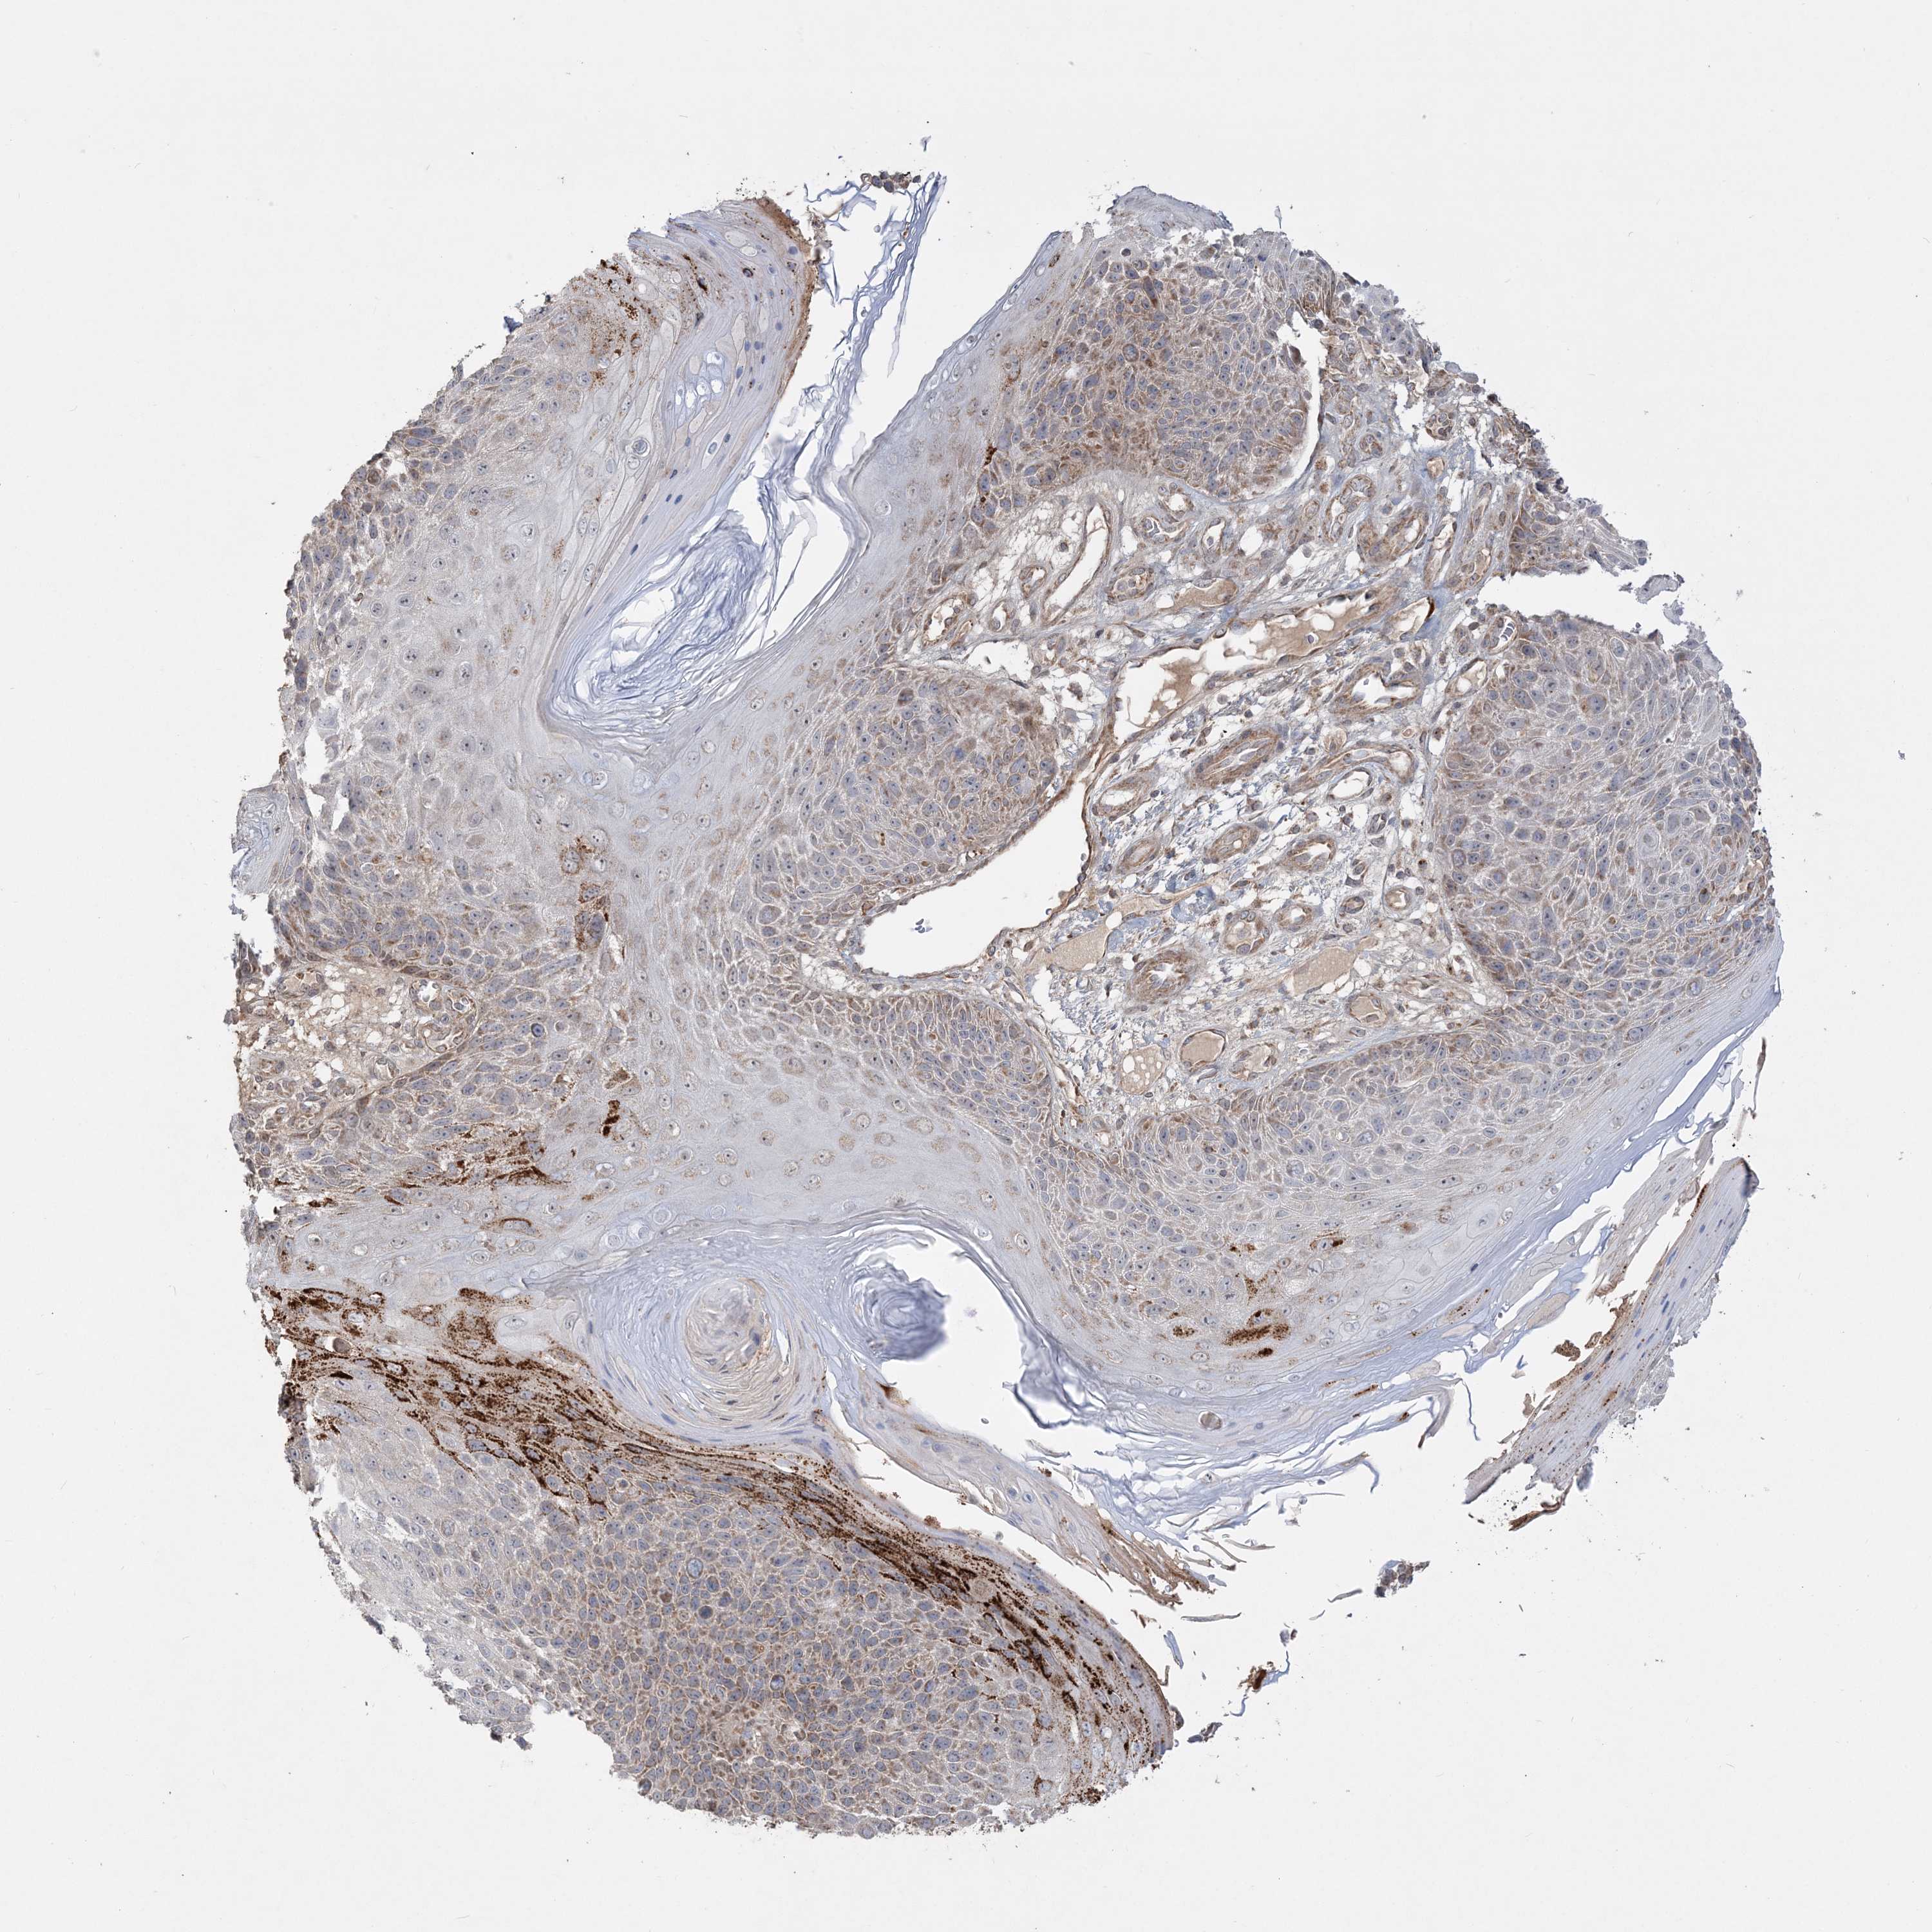

Basal cell and squamous cell cancer

SKIN CANCER - Protein expressioni

A mouse-over function shows sample information and annotation data. Click on an image to view it in a full screen mode. Samples can be filtered based on level of antibody staining by selecting one or several of the following categories: high, medium, low and not detected. The assay and annotation is described here.

Antibody stainingi

Antibody staining in the annotated cell types in the current human tissue is reported as not detected, low, medium, or high, based on conventional immunohistochemistry profiling in selected tissues. This score is based on the combination of the staining intensity and fraction of stained cells.

Each image is clickable and will lead to virtual microscopy that enables deeper exploration of all samples and also displays staining intensity scores, fraction scores and subcellular localization as well as patient and tissue information for each sample.

Antibody HPA036560

Antibody HPA036561

Staining

High

Medium

Low

Not detected

Intensity

Strong

Moderate

Weak

Negative

Quantity

>75%

75%-25%

<25%

None

Location

Nuclear

Cytoplasmic/membranous

Cytoplasmic/membranous,nuclear

Squamous cell carcinoma, NOS

Squamous cell carcinoma, metastatic, NOS